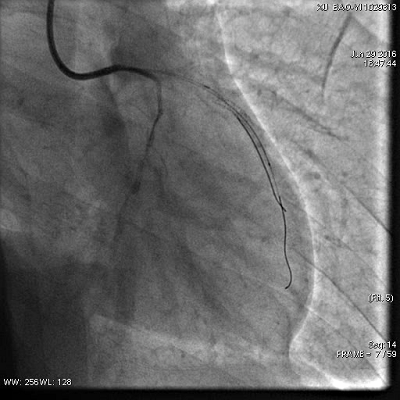

6.30凌晨复查冠脉造影

术后爱络加量为0.10mg/kg/min,减慢心率,降低心肌氧耗

胸闷痛缓解(6.30)